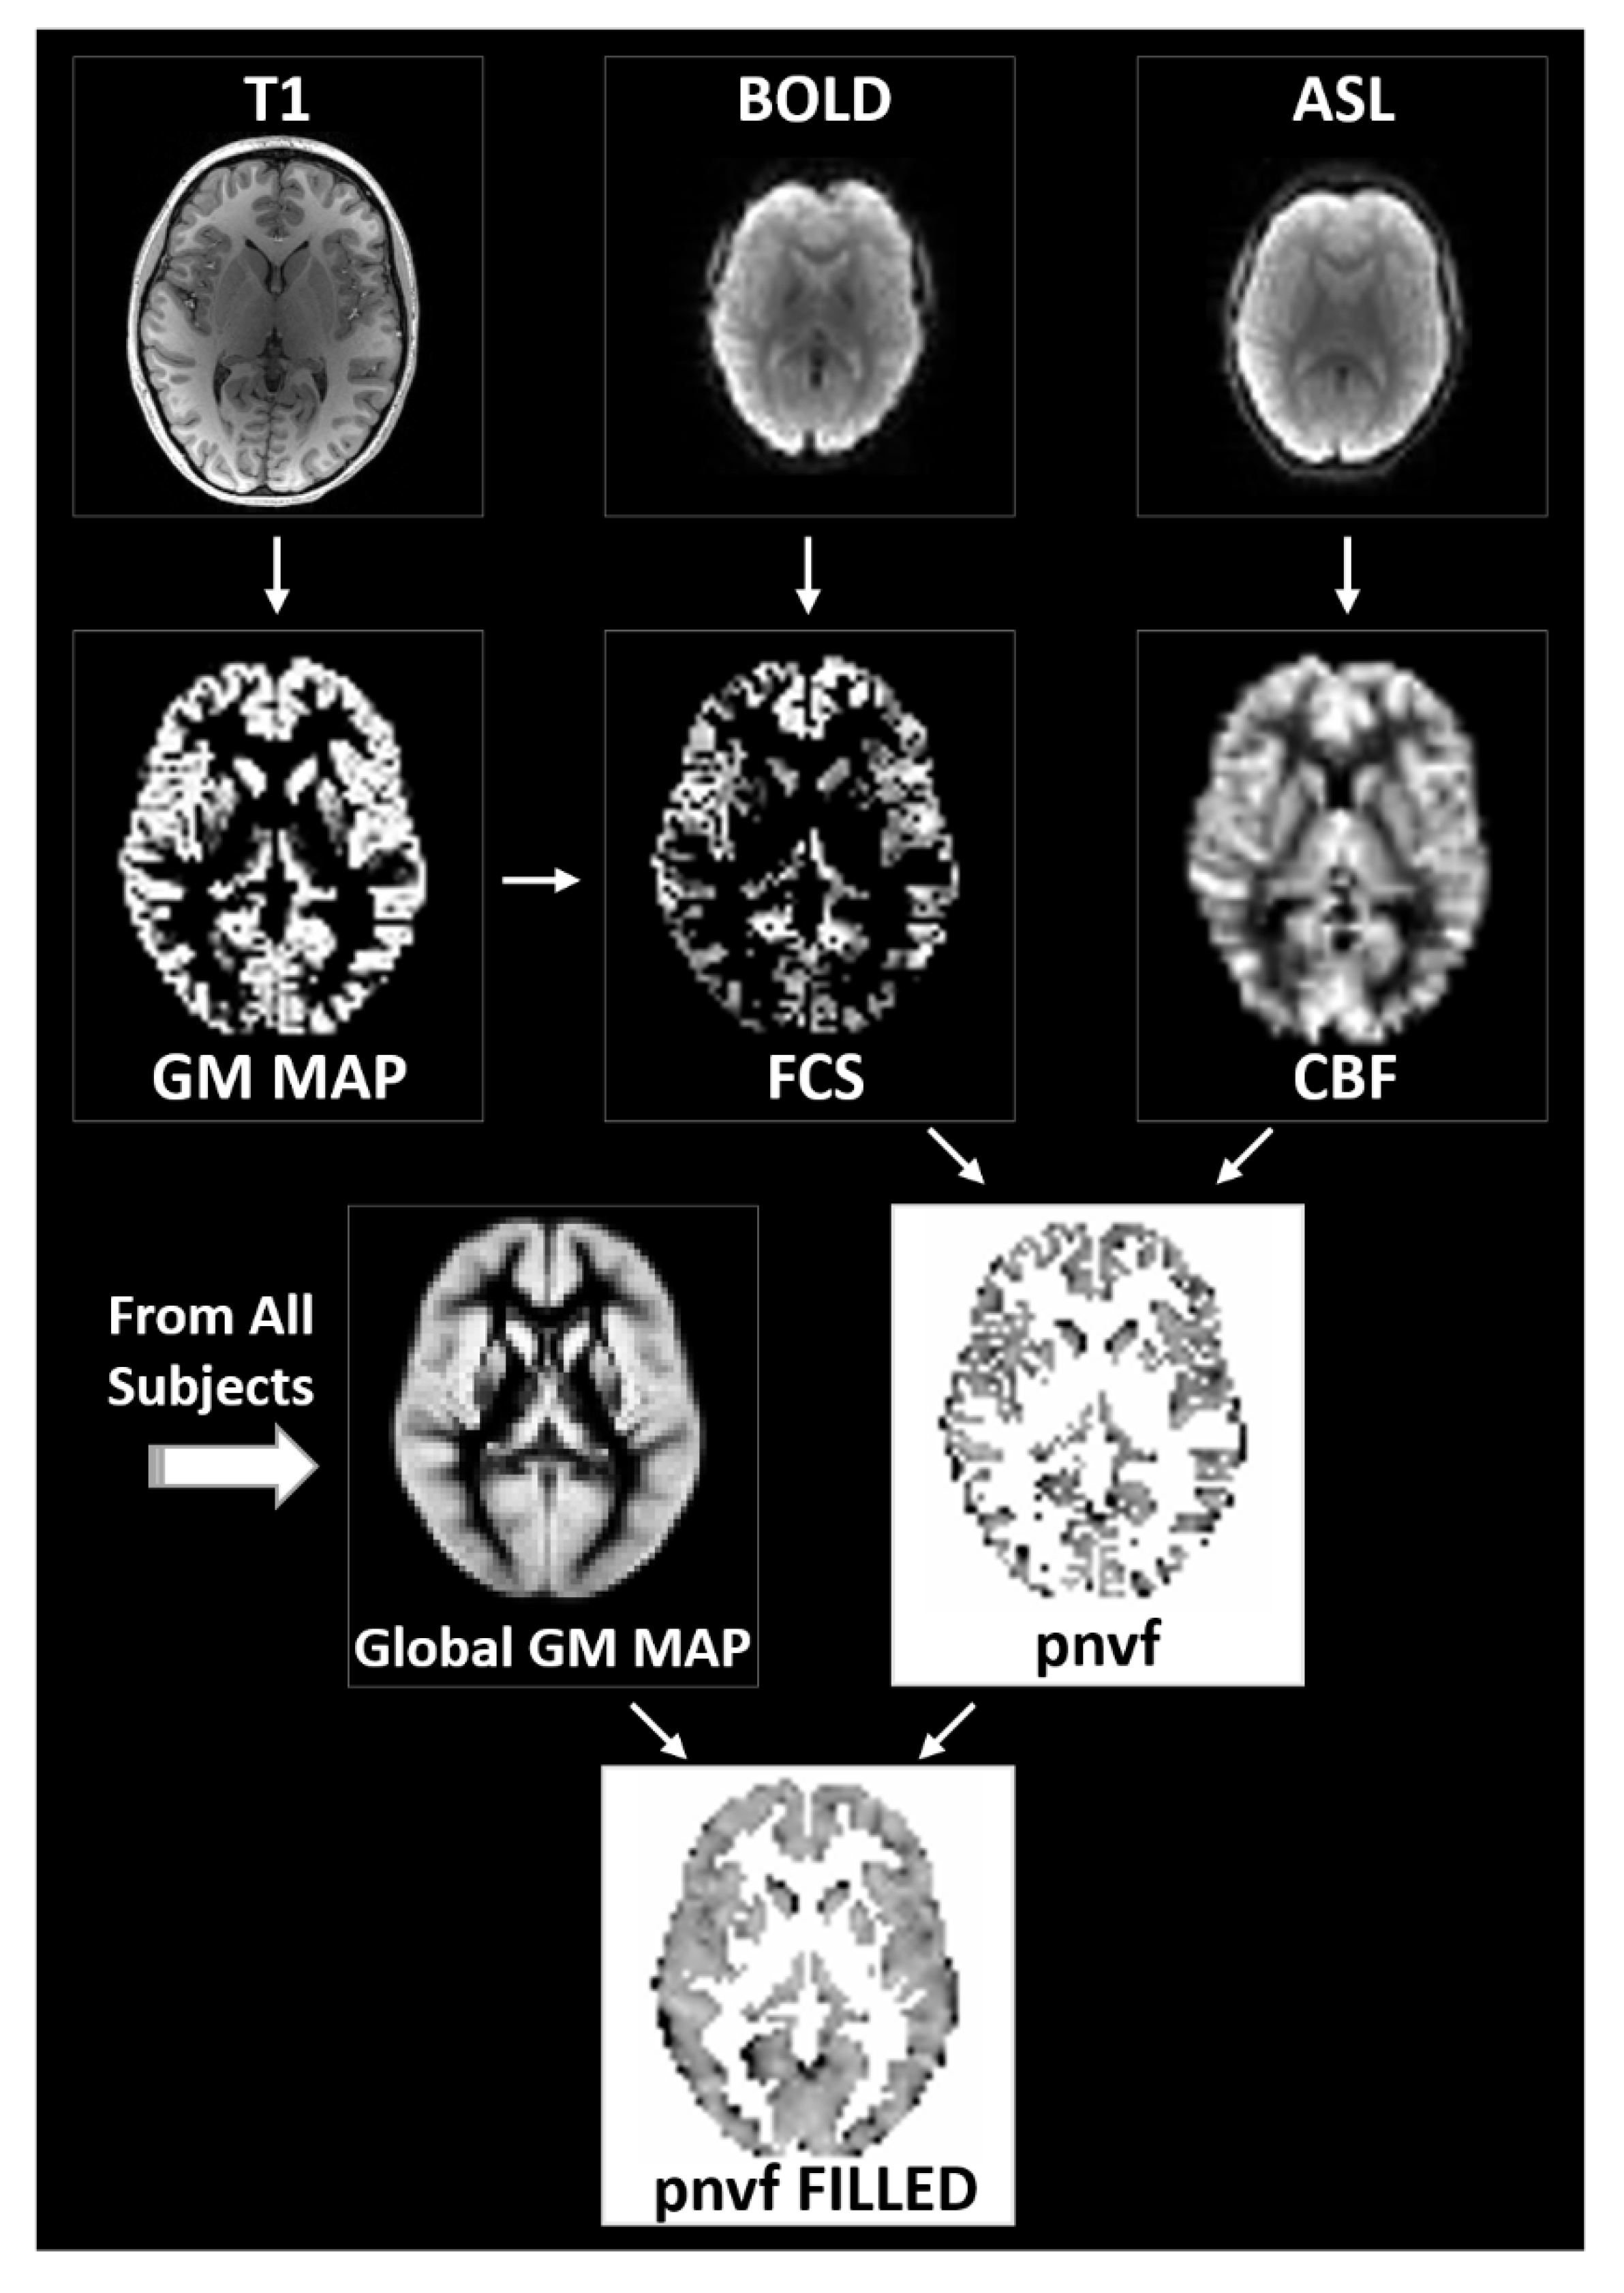

An overview of the process to estimate Pnvf is given in Figure 1 and described in detail below. The whole-brain images were segmented into gray matter, white matter, and cerebrospinal fluid (CSF), and the gray matter images were transformed into standardized Montreal Neurological Institute (MNI) space. After transformation of the resting-state BOLD acquisitions into MNI space, the FCS in a gray matter voxel was computed as the averaged threshold correlation coefficient between its time course and the time courses of all other gray matter voxels. From the pCASL acquisitions, CBF is computed from the contrast created via “labeling” or inverting incoming blood from the carotid arteries prior to perfusing into the tissue; the CBF maps were likewise transformed into MNI space. Although Pnvf could then be estimated on a voxelwise basis as the ratio of CBF/FCS, due to noise considerations (FCS being a noisier measurement compared to CBF), we preferred to use the negative ratio of FCS/CBF. Between-participant analyses were performed for all voxels in a global gray matter mask; missing data in a participant (e.g., due to imperfect spatial registration) were filled in via trilinear interpolation from neighboring voxels.

Figure 1.

Flowchart of the data processing routines for the estimation of the proxy for neurovascular function (Pnvf). Gray matter voxels are determined via segmentation of the whole-brain anatomical T1 images (left). From the BOLD resting-state data, functional connectivity strength (FCS) is computed voxelwise as the average correlation coefficient between a gray matter voxel time course and the time courses of all other gray matter voxels (center). From the ASL data, cerebral blood flow (CBF) maps are computed based on the difference between the labeled and unlabeled acquisitions (right). All maps are transformed into standardized Montreal Neurological Institute (MNI) space. Pnvf is computed on a voxelwise basis as the negative of the FCS/CBF ratio for all voxels in the global gray matter mask; missing values are filled in via trilinear interpolation (bottom).